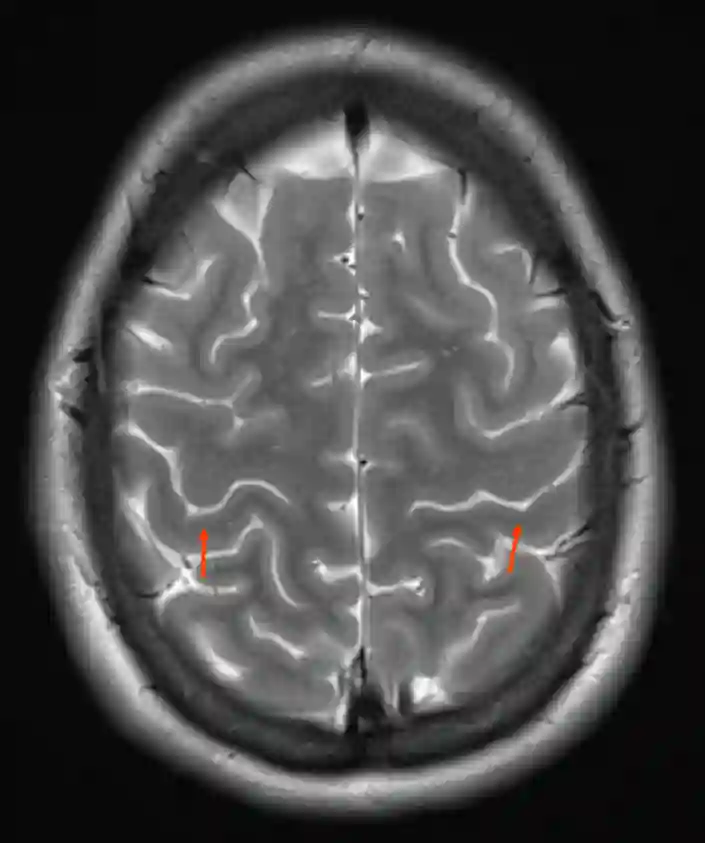

Darstellung des Gyrus postcentralis (roter Pfeil) in einem axialen T2 gewichtetem MRI Bild.